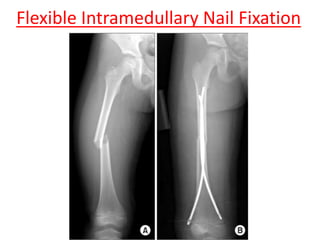

Flexible Intramedullary Nail Fixation